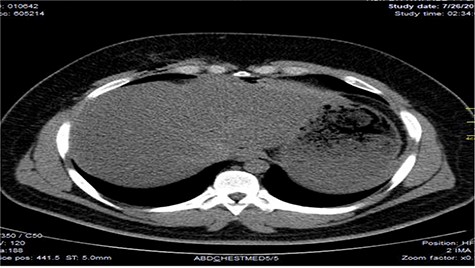

Chest X-ray was normal as shown in Fig. 1. Focused abdominal sonography for trauma (FAST) scan showed mild left perihepatic collection necessitating a thoracoabdominal computerized tomography (CT)-scan which showed external oblique muscle laceration with intermuscular air lucencies and grade 2 hepatic injury as shown in Figs 2–4. Other blood work-up were normal. No other injury was found on secondary survey. His wound was explored under local anaesthesia, primarily repaired, and he was discharged after 24 h of close observation.

Image showing air lucencies in the right intercostal muscles and subcutaneous tissue around the lower right parasternal region.

Showing lucent air densities tracking through the right intercostal muscles and abutting on the liver in the epigastrum with associated subcapsular haematoma in the left lobe of the liver.

Image shows lucent air densities tracking through the subcapsular haematoma in the left lobe of the liver anterior to the pylorus of the stomach.